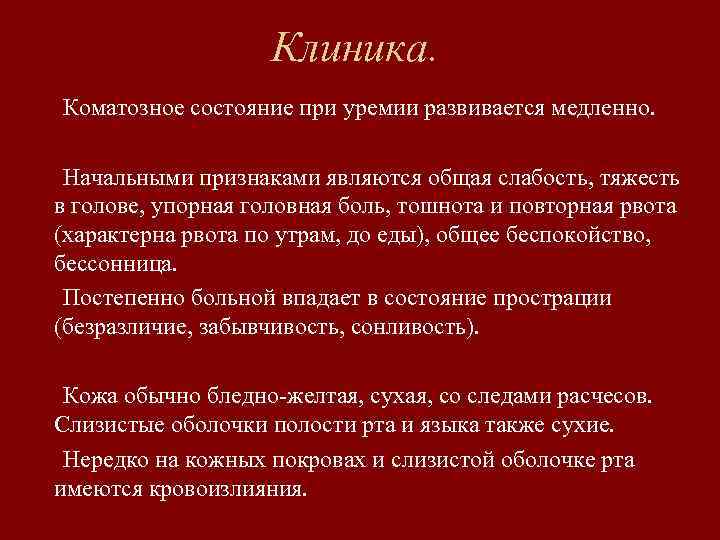

Клиника. Коматозное состояние при уремии развивается медленно. Начальными признаками являются общая слабость, тяжесть в голове, упорная головная боль, тошнота и повторная рвота (характерна рвота по утрам, до еды), общее беспокойство, бессонница. Постепенно больной впадает в состояние прострации (безразличие, забывчивость, сонливость). Кожа обычно бледно-желтая, сухая, со следами расчесов. Слизистые оболочки полости рта и языка также сухие. Нередко на кожных покровах и слизистой оболочке рта имеются кровоизлияния.

Клиника. Коматозное состояние при уремии развивается медленно. Начальными признаками являются общая слабость, тяжесть в голове, упорная головная боль, тошнота и повторная рвота (характерна рвота по утрам, до еды), общее беспокойство, бессонница. Постепенно больной впадает в состояние прострации (безразличие, забывчивость, сонливость). Кожа обычно бледно-желтая, сухая, со следами расчесов. Слизистые оболочки полости рта и языка также сухие. Нередко на кожных покровах и слизистой оболочке рта имеются кровоизлияния.